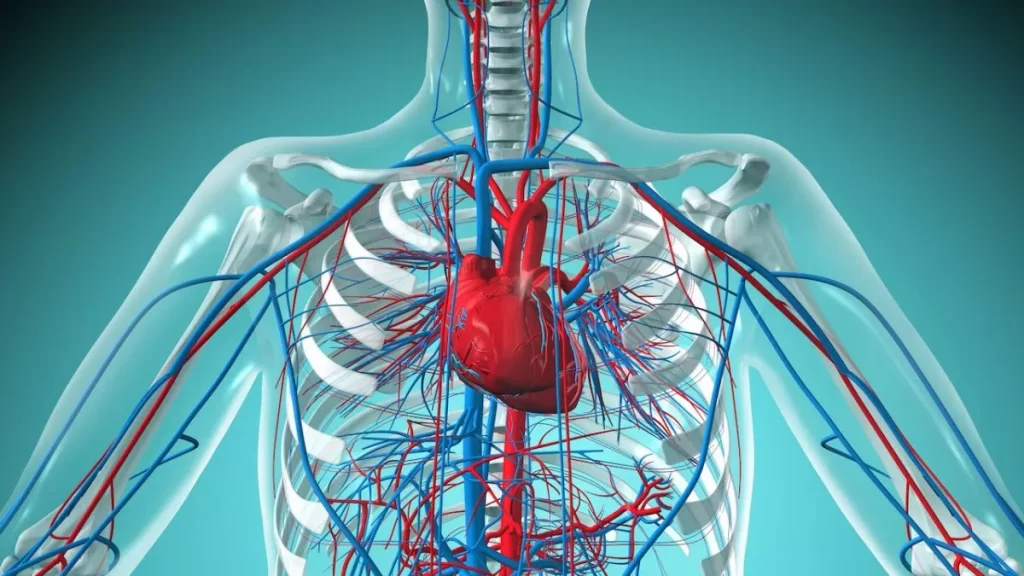

بیماریهای قلبی و عروقی یکی از مهمترین عوامل مرگومیر در جهان محسوب میشوند، اما خبر خوب این است که با رعایت چند نکته ساده و تغییر سبک زندگی میتوان تا حد زیادی از بروز این بیماریها پیشگیری کرد. قلب، موتور اصلی بدن است و سلامت آن مستقیماً بر کیفیت زندگی ما تأثیر میگذارد.

علل اصلی بروز بیماریهای قلبی و عروقی

شناخت عوامل خطر، اولین قدم در مسیر پیشگیری است. مهمترین دلایل ابتلا به بیماریهای قلبی عبارتاند از: